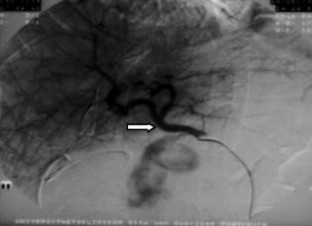

Wir berichten über das diagnostische und therapeutische Vorgehen anhand von 7 Patienten mit Blutungen aus der A. gastroduodenalis (n=5) nach pankreaschirurgischen Interventionen bei Pankreaskopfkarzinom, Rezidiv eines Liposarkoms und chronischer Pankreatitis, der A. hepatica communis (n=1) bei chronischer Pankreatitis und der A. mesenterica superior (n=1) nach akuter Pankreatitis. Anhand von 4 Kasuistiken werden unsere Erfahrungen mit der Implantation von Stentgrafts (Hemobahn®-Prothesen) vermittelt. Den Vorteil der Stentgrafts sehen wir in der sofortigen Blutstillung bei fehlendem Kontakt der Endoprothese zu infiziertem Gewebe und Erhalt der Perfusion des abhängigen Organs. Unsere positiven Erfahrungen mit diesen interventionellen Therapieverfahren erfordern jedoch weitere klinische Untersuchungen, wobei im Mittelpunkt die Indikationen, die technische Erfolgsrate, die stentbedingten Komplikationen und die Langzeitverläufe stehen sollten.

Spontaneous or postoperative hemorrhage into the abdominal cavity due to inflammatory vessel arrosion represents an uncommon but menacing situation. According to the literature, such hemorrhage is associated with a lethality of nearly 2%. Therapeutical options include reoperation and interventional radiological techniques such as endovascular catheter techniques with stent graft implantation or the embolization of vessels. We report on the management of seven cases with hemorrhage either from the gastroduodenal artery (n=5) following pancreatic surgery for pancreatic carcinoma, liposarcoma, and chronic pancreatitis or from the common hepatic artery (n=1) and the superior mesenteric artery (n=1) following chronic pancreatitis. The present article describes our experiences with stent graft implantation (hemobahn prosthesis) in four cases. Based on these experiences, we see the advantages of stent grafts in primary hemostasis without any contact to infected tissue and the preservation of regular perfusion. However, further clinical data are required focussing on indication, technical success rates, stent-related complications, and long-term outcome.

Abb. 1